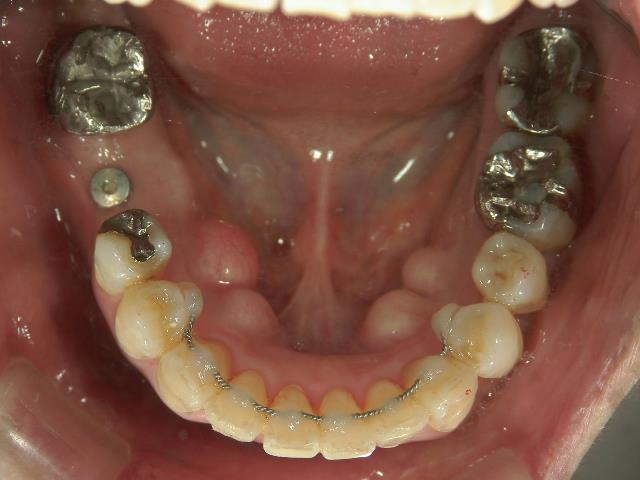

矯正歯科 治療前